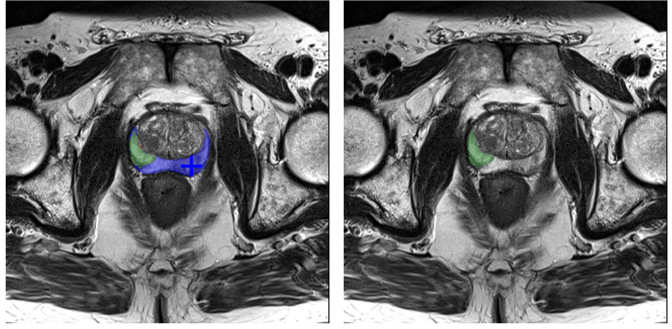

2. Privileged Information. While M2 writes from the agent’s perspective, it views a privileged “oracle” image. As shown in Fig. 7 (Left), this image explicitly visualizes segmentation errors: a Green Mask for True Positives, a Red Mask for False Positives (over-segmentation), and a Blue Mask for False Negatives (under-segmentation). It also indicates the “correct” next action (Positive/Negative point).

((a))

Refer to caption

((b))

Figure 7: Comparison of the “Oracle” view (for M2) and the “Agent” view (for M1) used in SFT reasoning generation.

Notably, this agent-visible mask (green) is the sum of the oracle’s True Positive (green) and False Positive (red) areas. M1 must learn to infer the expert’s corrective reasoning from this limited perspective.